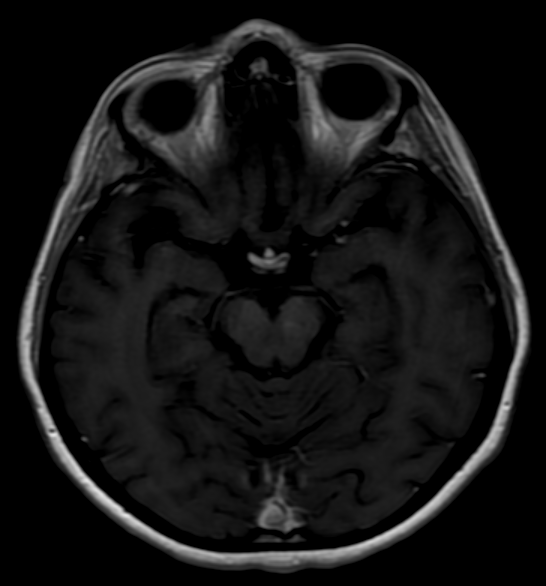

Objetivo: Relatar o caso de recidiva de herpes-zoster (HZ) em paciente com esclerose múltipla (EM) em uso de tratamento imunomodulador (natalizumabe) com evolução favorável. Descrição de caso: Mulher de 39 anos com diagnóstico de EM há 1 ano e 6 meses, previamente tratada com interferon 1a, começou tratamento com natalizumabe, desenvolvendo HZ após três meses de tratamento. HZ foi tratado com aciclovir, por sete dias, via oral. Seguimento ambulatorial após três meses de tratamento mostrou resolução completa das lesões, sem desencadeamento de neuralgia pós-herpética. Conclusões: As novas terapias para a EM podem estar relacionadas a diferentes tipos de efeitos adversos. Nem todos os casos de HZ, associados com novas terapias para EM, evoluem de forma desfavorável. Estudos são necessários para reconhecer os fatores de riscos para as formas graves de HZ em tais pacientes.